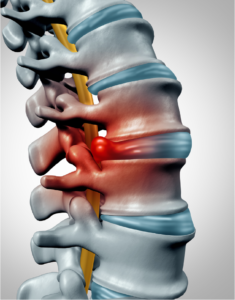

Herniated Disc

Herniated disc is a condition in which the outer fibers (annulus) of the intervertebral disc are damaged causing the soft inner material of the nucleus…

Lumbar Disc Herniation

Lumbar disc herniation is the most common cause of low back pain and leg pain (sciatica). The lumbar intervertebral discs are flat and round.